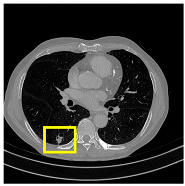

3.4.2. Representative Cases with Segmentation Challenges on the MEF-PN35 Dataset

To complement the quantitative evaluation, we present a set of representative cases from the clinical dataset that exhibited typical segmentation challenges. These cases were selected to reflect diverse morphological characteristics observed in pulmonary nodules, such as spiculated boundaries, small size, vessel adherence, pleural attachment, cavitation, and clear isolation. Rather than aiming for exhaustive categorization, our intent is to highlight a range of practical difficulties encountered in real-world scenarios and to qualitatively assess how different boundary-aware loss functions respond to these variations. Each challenge is labeled (C1) through (C5) in Table 10 and is consistently referenced in the corresponding detailed illustrations that follow.

Following the summary in Table 11, we present detailed visual comparisons for selected representative cases, each corresponding to a specific segmentation challenge. These cases are consistently labeled using the Challenge ID (CID) codes defined in Table 9 to facilitate cross-referencing between the summary and the case illustrations. Each table reports segmentation results across three loss configurations (Sobel, Laplacian, and Hausdorff) using five columns. Loss indicates the boundary loss formulation applied in each case, where Dice loss is combined with a boundary term computed using Sobel, Laplacian, or Hausdorff operators. The Segmentation Result column shows four images side by side: the input CT patch, the manual ground truth, the model prediction, and a color-coded difference map between ground truth and prediction. In this map, green indicates true positives, blue represents true negatives, red corresponds to false positives, and yellow denotes false negatives. The final column, Attention Map, presents Grad-CAM visualizations derived from one of the Adaptive Attention Fusion (AAF) layers in the encoder path. These maps illustrate the spatial focus of the model, with red/yellow regions indicating strong attention and lighter or neutral tones indicating lower activation. All six cases are presented in detail in Table 11, Table 12 and Table 13, providing a comprehensive qualitative analysis of how each loss configuration performs under specific segmentation challenges observed in real clinical data.

Beyond quantitative metrics, the model has also demonstrated strong performance across a diverse range of challenging clinical scenarios. As detailed in Table 11, Table 12 and Table 13, CAAF-ResUNet effectively handled representative cases including nodules with clear boundaries (C1), small size (C2), blurred margins (C3a–C3b), cavitary structures (C4), and spiculated edges (C5). These examples underscore the model’s ability to adapt to a wide spectrum of morphological complexities often encountered in routine CT interpretation.